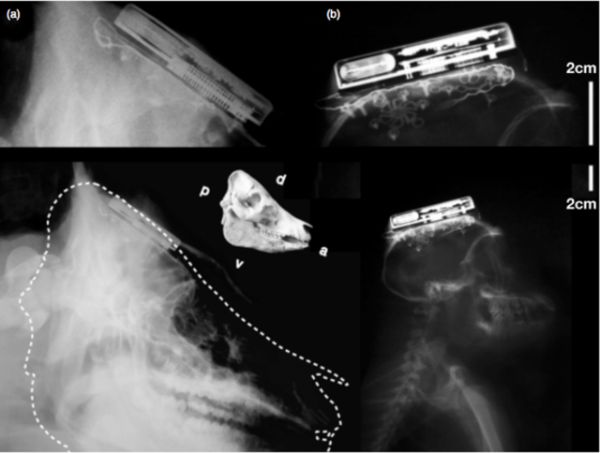

據(jù)外媒報(bào)道,近日,來(lái)自布朗大學(xué)的研究人員研發(fā)出了全球首個(gè)通過(guò)無(wú)線方式連接的腦機(jī)接口。雖然早前也曾經(jīng)出現(xiàn)過(guò)多種腦機(jī)接口,但它們?nèi)紵o(wú)法通過(guò)無(wú)線連接,所以常常導(dǎo)致穿戴者的行動(dòng)受限。而現(xiàn)在由布朗大學(xué)研發(fā)的腦機(jī)接口將打破這一局限。

據(jù)介紹,這個(gè)無(wú)線腦機(jī)接口個(gè)頭只有一個(gè)火柴盒那么大,它可以放在穿戴者的頭骨進(jìn)行檢測(cè)。它將可以將檢測(cè)到的數(shù)據(jù)傳輸給在1米開(kāi)外的電腦。而安放在其中的200mAh鋰離子電池可以讓這個(gè)設(shè)備續(xù)航7個(gè)小時(shí)。